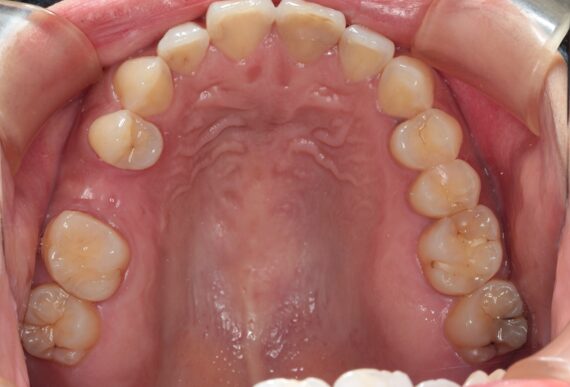

39歳男性